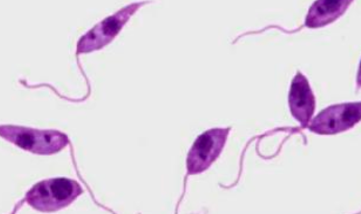

(1) Amastigote (2) Promastigote (3) Epimastigote (4) Trypomastigote

State the 4 morphologic states (stages) of tissue flagellates from top to bottom.

Undulating membrane

extension of cytoplasmic membrane, helps in locomotion (wavelike and reversible movements)

Axoneme

helps with springlike flexibility

Kinetoplast

crucial for replication of the parasite

contains the DNA of the parasite

Nucleus

Trypomastigote

What morphologic state is this flagellate?

(a) Epimastigote (b) Trypomastigote (c) Amastigote

State the morphologic state in order from left to right.